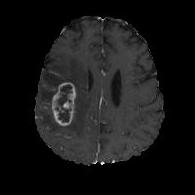

(a) (b) (c) (d)

Boundary Stream:

Fig. 2 demonstrates the output of each of the attention layers in our dedicated boundary stream. In essence, each attention layer progressively localizes the tumor and refines the boundaries. The first attention layer has learned rough estimate of the boundaries around the tumor and localized it, whereas the second and third layers have learned more fine-grained details of the edges and boundaries, refining the localization. Moreover, since our architecture leverages a dilated spatial pyramid pooling to merge the learned feature maps of the regular segmentation stream and the boundary stream, multiscale regional and boundary information have been preserved and fused properly, which has enabled our network to capture the small structural details of the tumor.

(a) (b) (c) (d) (e)